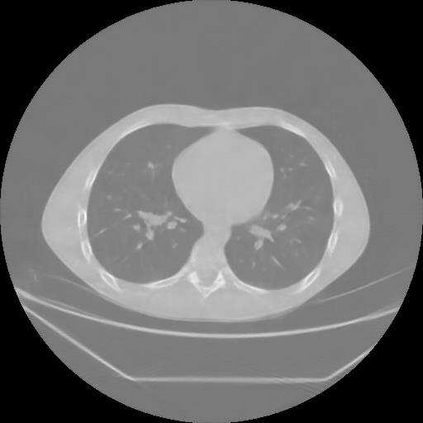

Sparse-view computed tomography (CT) is known as a widely used approach to reduce radiation dose while accelerating imaging through lowered projection views and correlated calculations. However, its severe imaging noise and streaking artifacts turn out to be a major issue in the low dose protocol. In this paper, we propose a dual-domain deep learning-based method that breaks through the limitations of currently prevailing algorithms that merely process single image slices. Since the scanned object usually contains a high degree of spatial continuity, the obtained consecutive imaging slices embody rich information that is largely unexplored. Therefore, we establish a cascade model named LS-AAE which aims to tackle the above problem. In addition, in order to adapt to the social trend of lightweight medical care, our model adopts the inverted residual with linear bottleneck in the module design to make it mobile and lightweight (reduce model parameters to one-eighth of its original) without sacrificing its performance. In our experiments, sparse sampling is conducted at intervals of 4{\deg}, 8{\deg} and 16{\deg}, which appears to be a challenging sparsity that few scholars have attempted before. Nevertheless, our method still exhibits its robustness and achieves the state-of-the-art performance by reaching the PSNR of 40.305 and the SSIM of 0.948, while ensuring high model mobility. Particularly, it still exceeds other current methods when the sampling rate is one-fourth of them, thereby demonstrating its remarkable superiority.